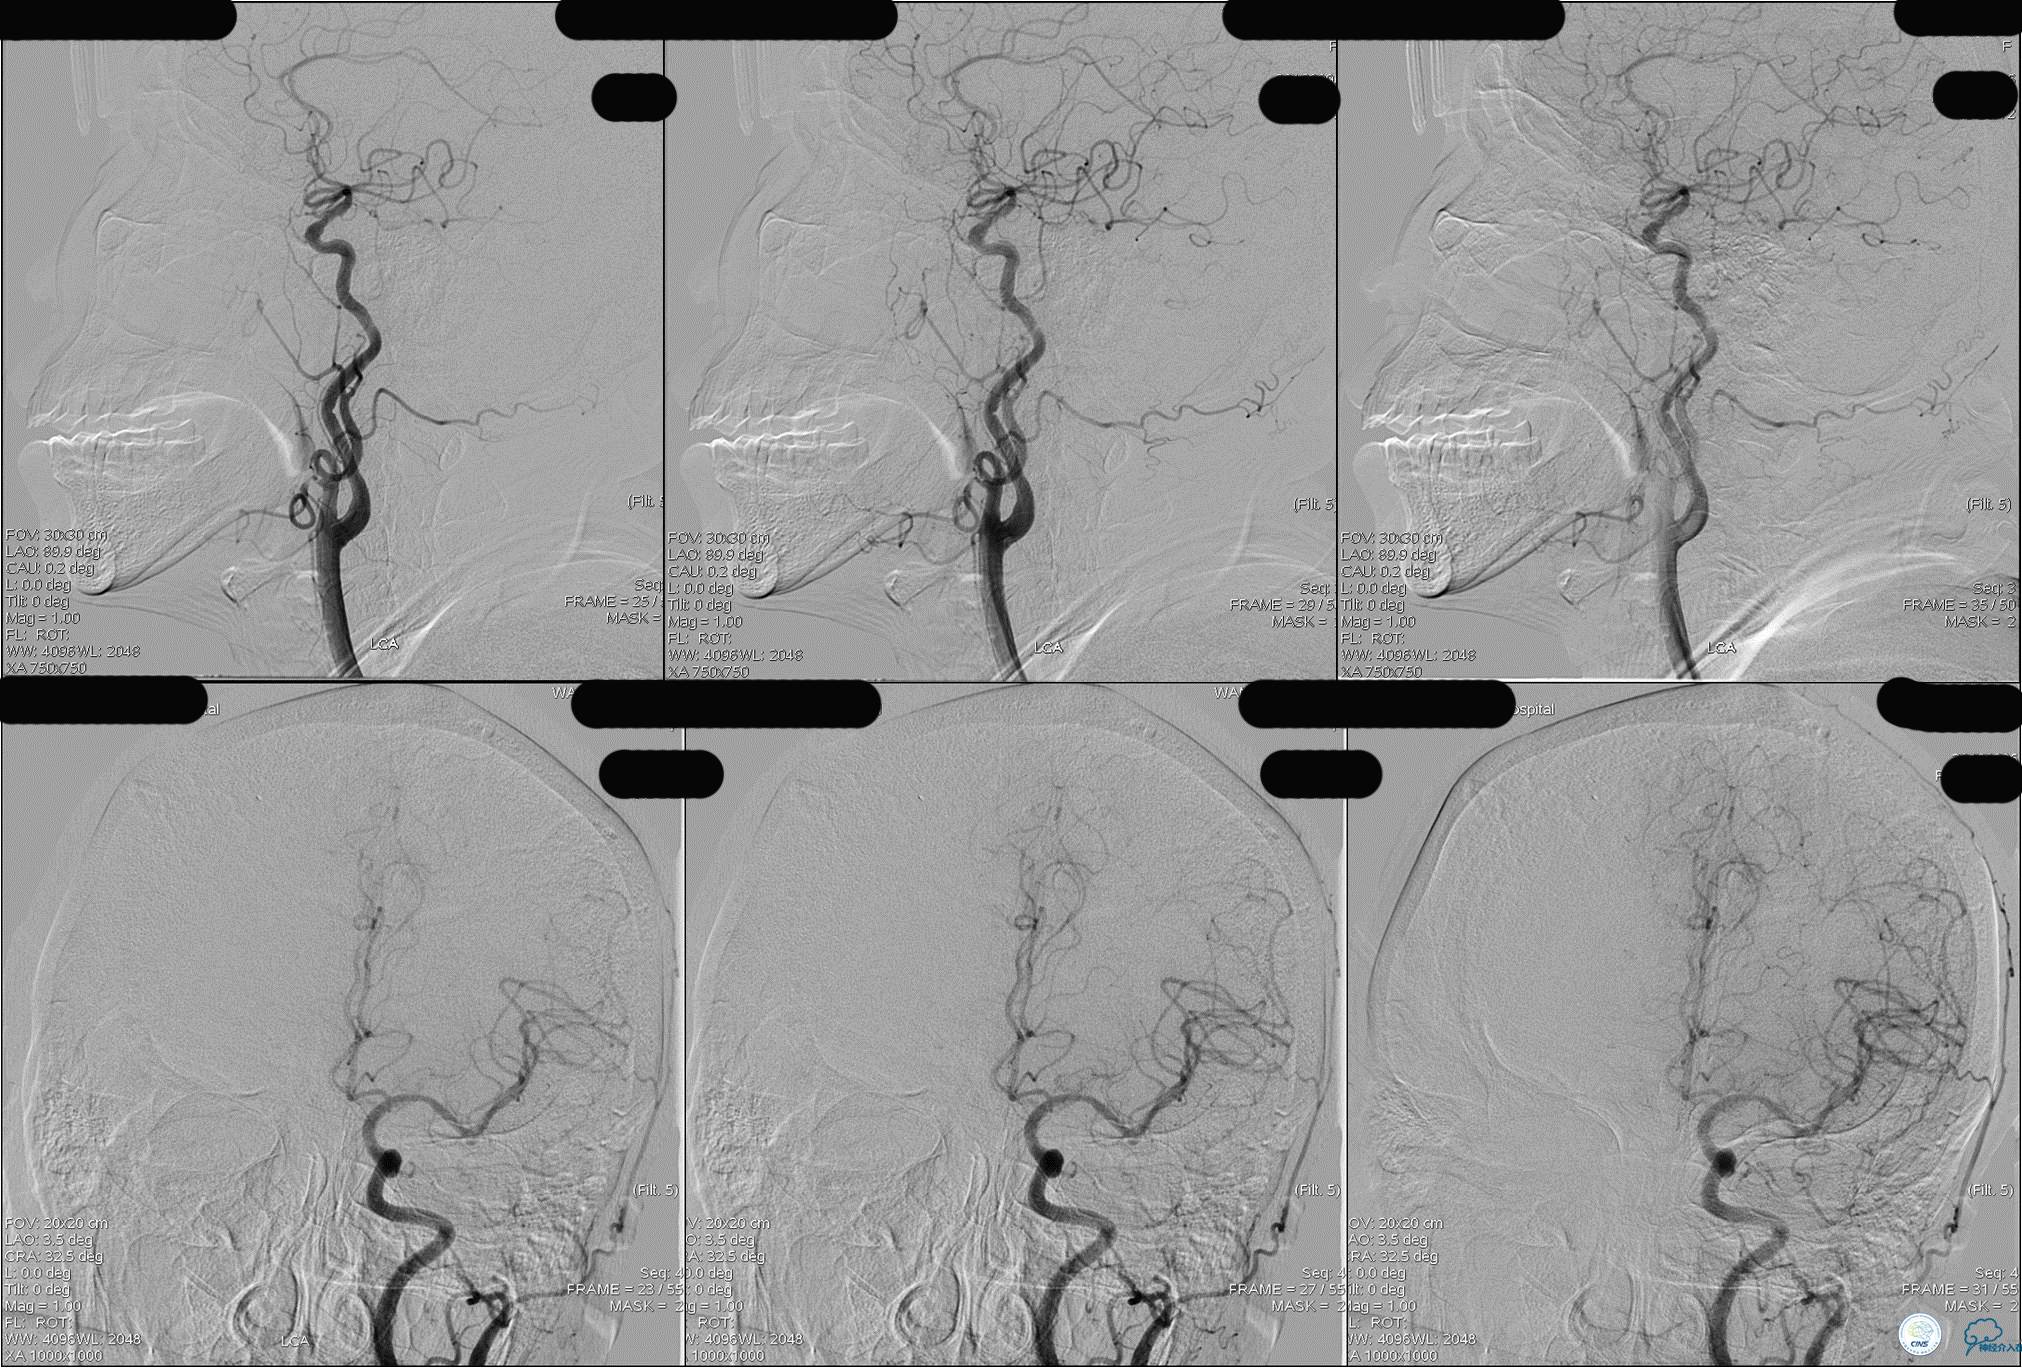

发病5.5小时给予股动脉穿刺

发现股动脉入路很差,斟酌经桡穿刺。

》DSA资料(左侧颈动脉)

》DSA资料(右侧颈动脉)